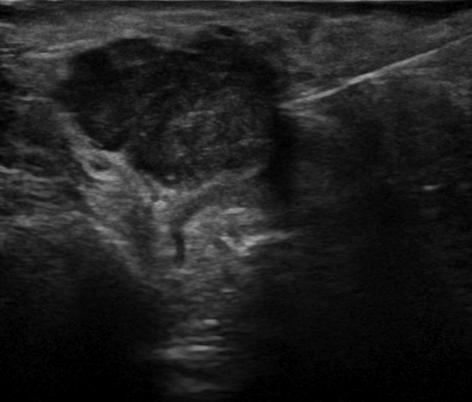

U tuyến nước bọt

U tuyến nước bọt - Ảnh 3

» Thông tin: Nam giới – 72 tuổi.

» Lâm sàng: Khối vùng mang tai.

# Ung thư biểu mô tuyến (Adenocarcinoma).